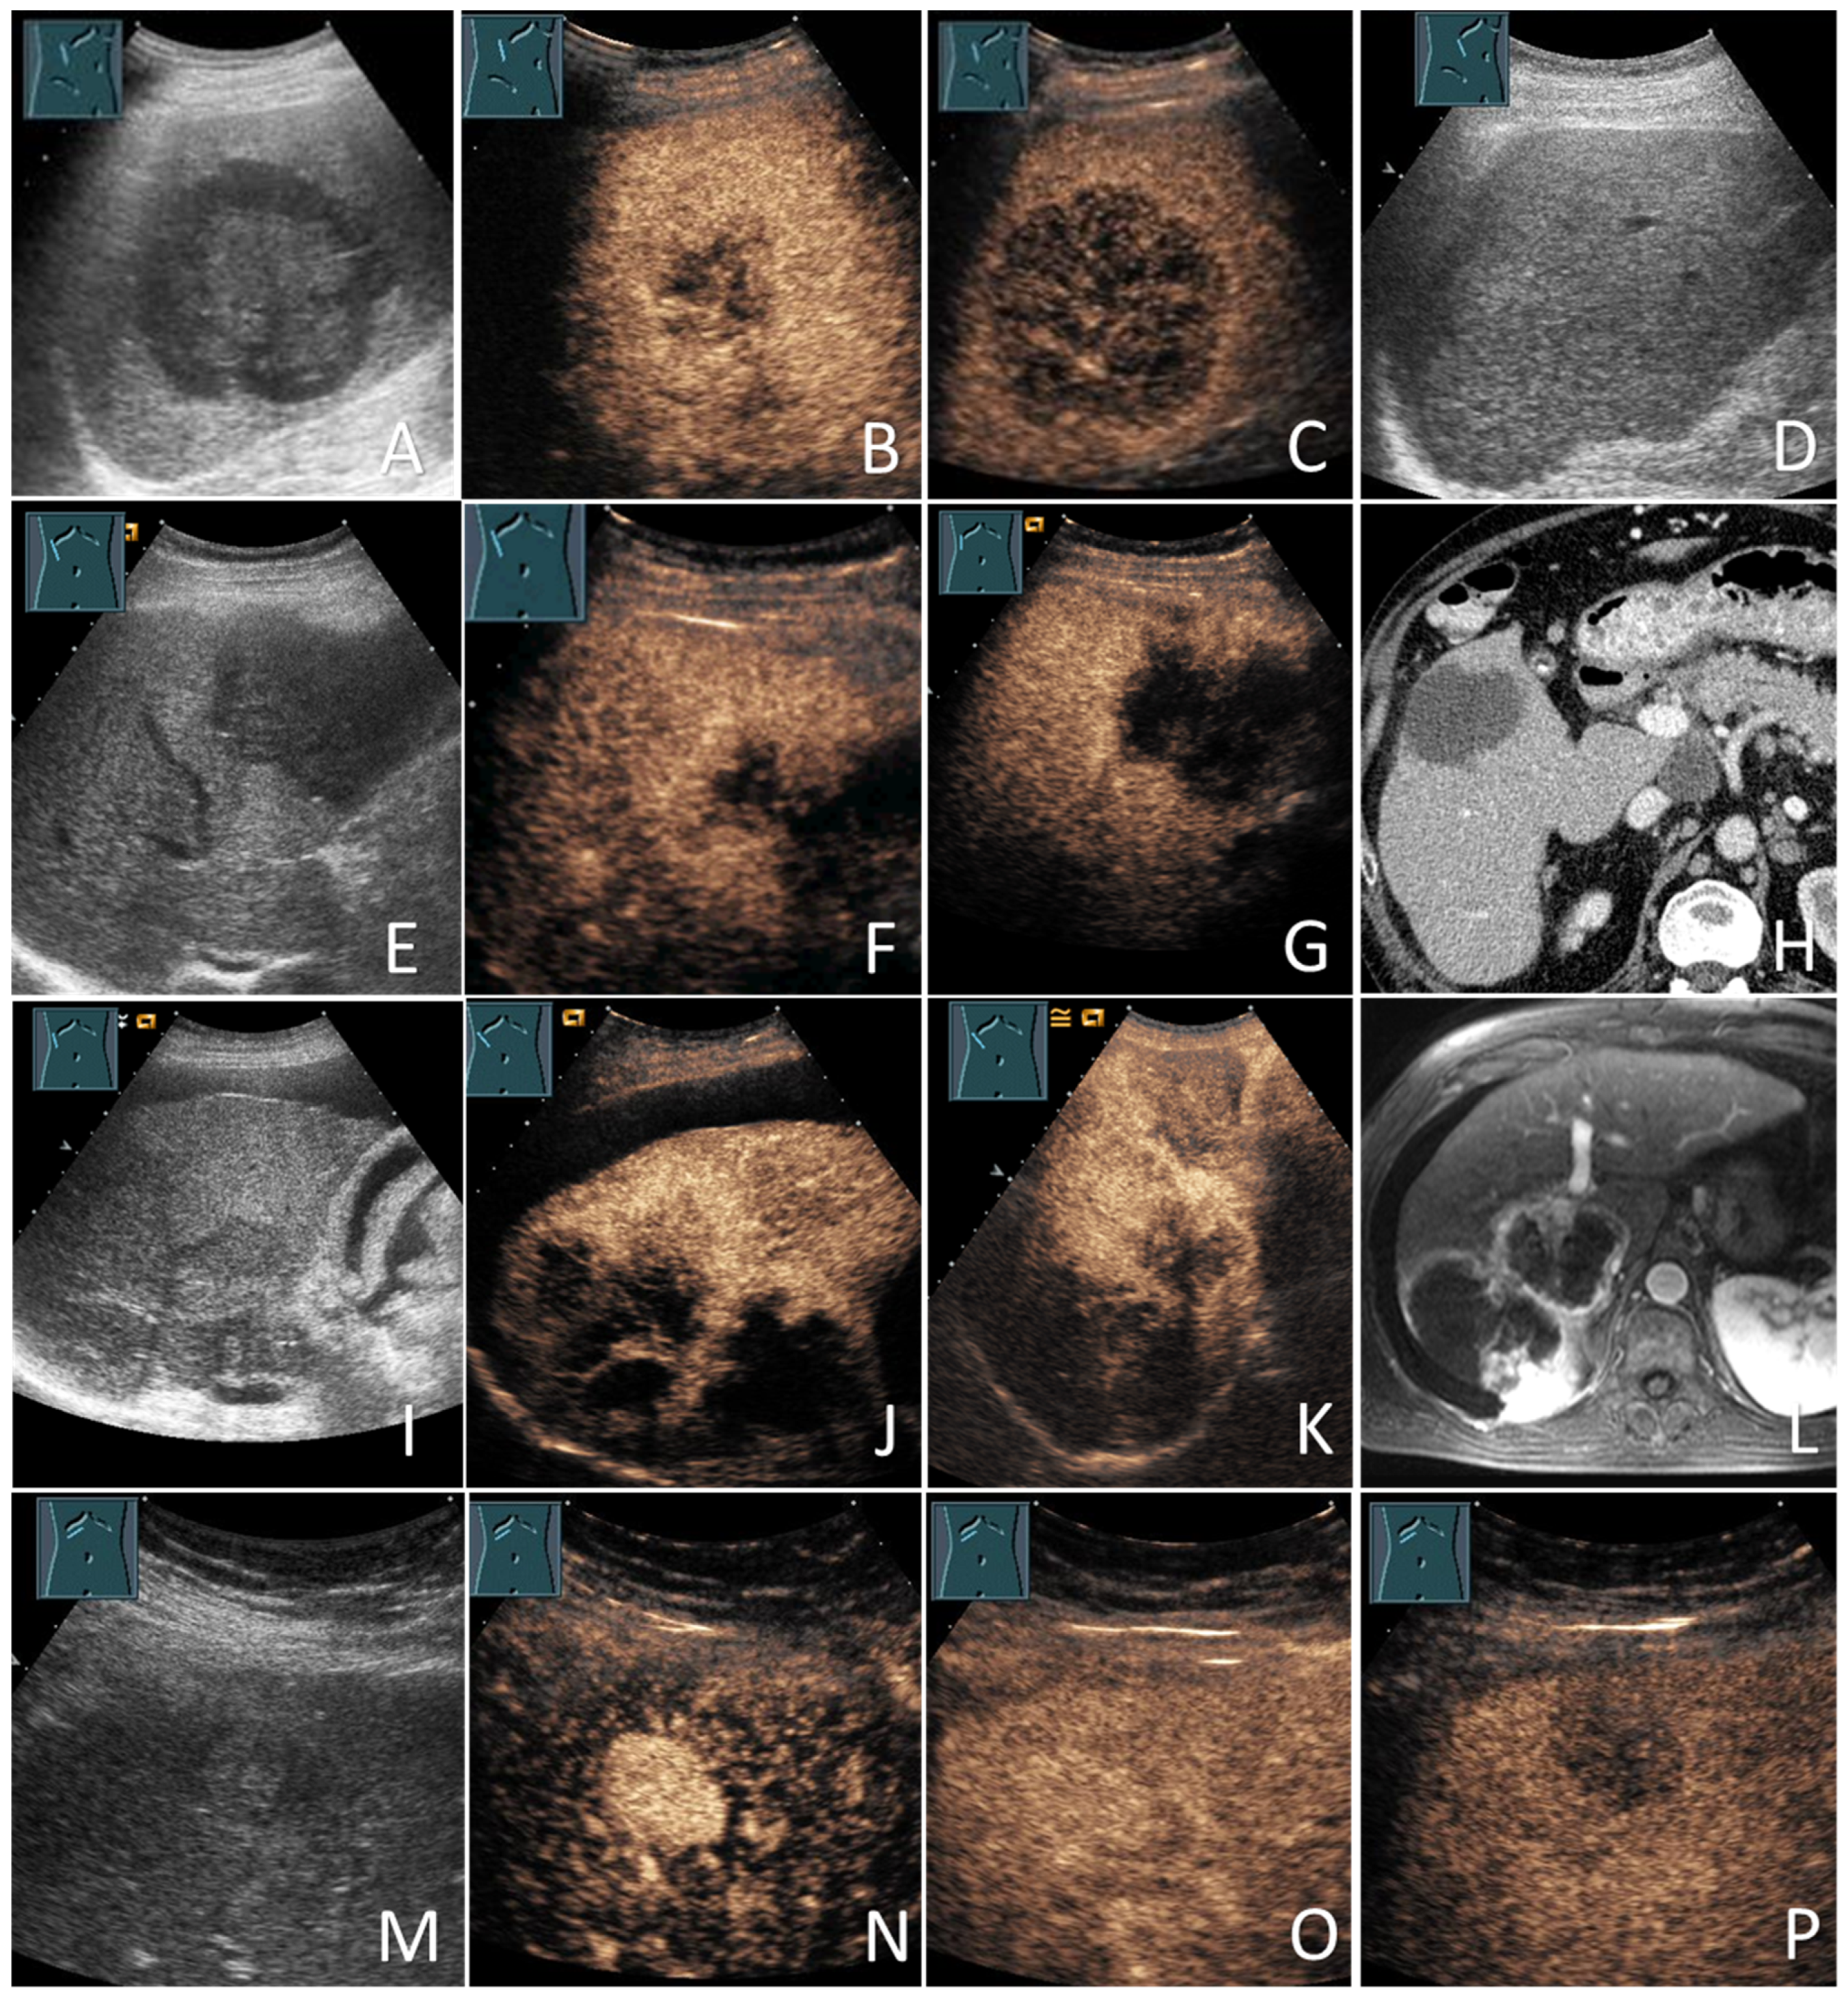

2.4. US and CEUS Examinations

2.5. Cross-Sectional Imaging